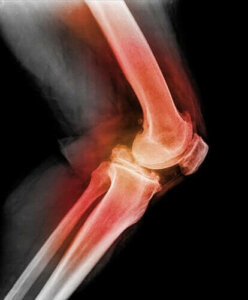

For å diagnostisere dislokasjon av kneskålen vil legen berøre kneskålen samt bøye kneet og bevege det i forskjellige retninger. Ved å bruke røntgen, MR- eller CT-scanning, kan de se bilder av den dislokerte kneskålen og andre kneskader.